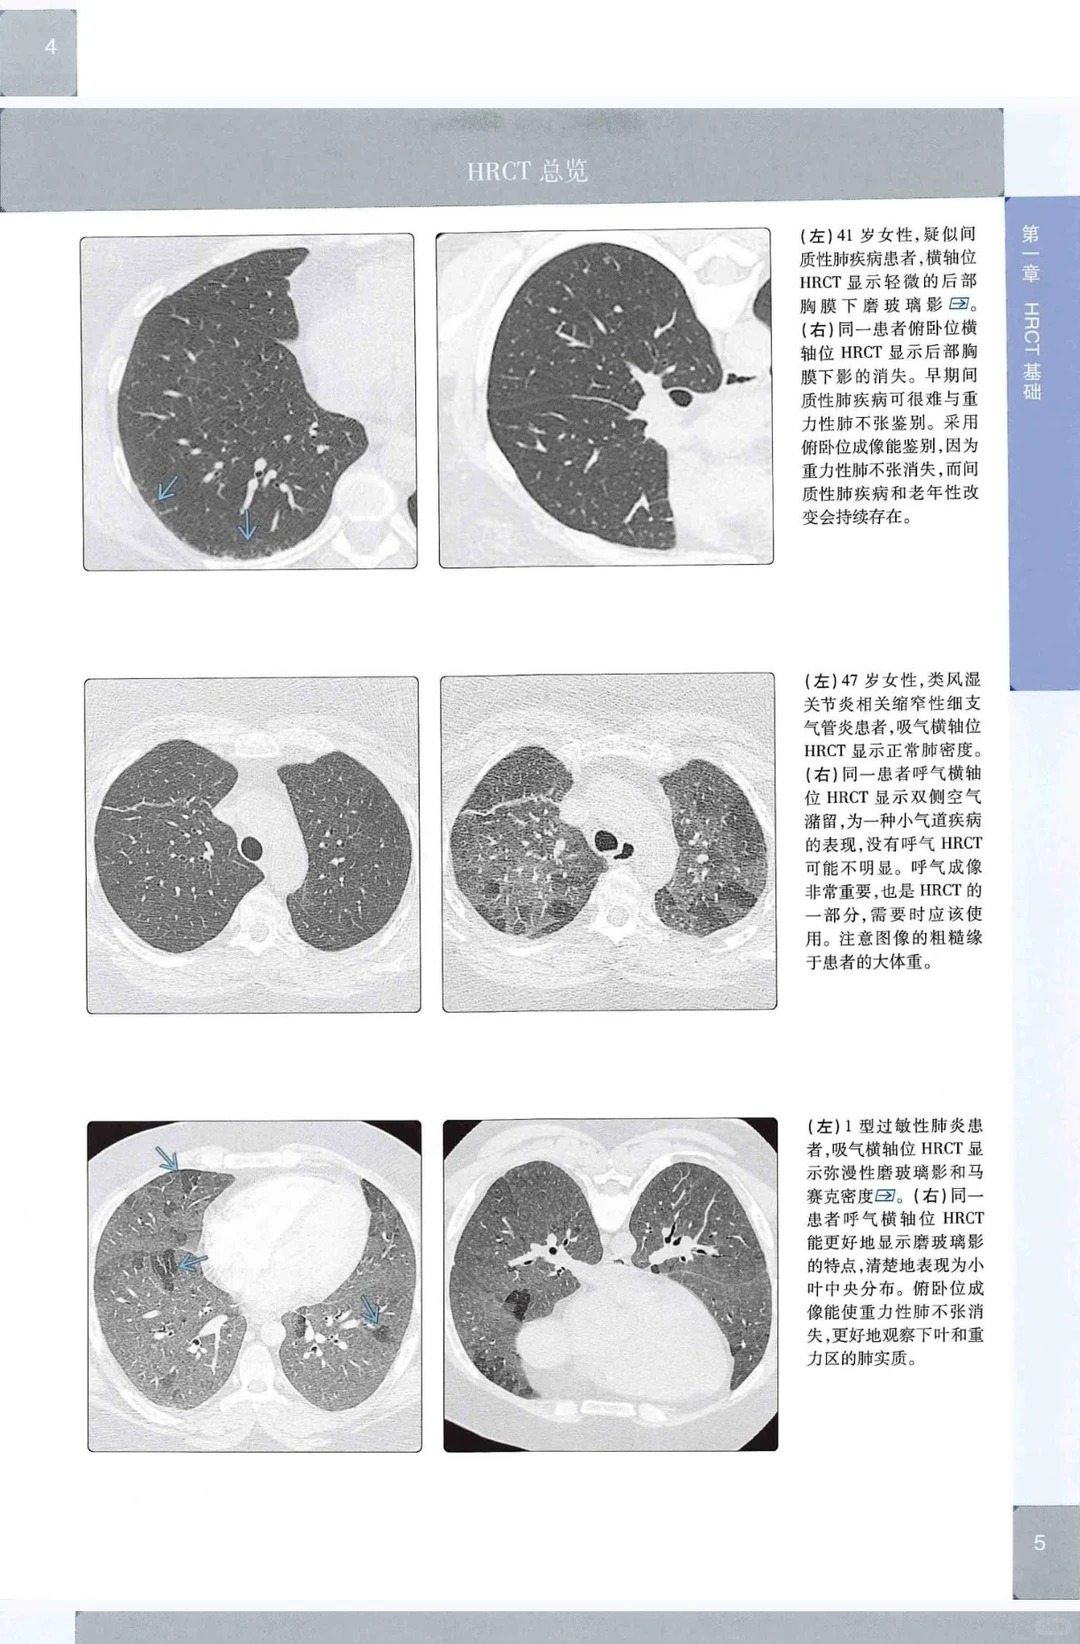

而《高清 肺部高分辨率CT(第2版)》,正是为解决所有医学影像相关人群的核心痛点而生。这本书在第1版基础上全面升级,图像质量肉眼可见提升,超高清影像将肺部病灶细节、纹理结构展现得淋漓尽致,小病灶、细微纹理也能清晰识别,彻底告别图像模糊的困扰;区别于单纯的“看图说话”,本书更注重诊断思维的强化,详细拆解分析逻辑与鉴别诊断思路,告诉读者“为什么是这个,而不是那个”,实战性拉满,助力建立科学的诊断思维;采用双维度讲解模式,既按疾病分类(感染、肿瘤、间质病、气道病...)展开,又按影像模式(网格、结节、实变...)梳理,结构清晰、层次分明,不管是系统学习还是针对性查漏补缺,都能快速找到对应内容,大幅提升学习与读片效率。

1. 超高清图像升级,细节拉满 对比第1版,图片质量肉眼可见提升,超高清影像精准呈现肺部病灶细节、纹理结构,小病灶、细微纹理也能清晰识别,告别模糊不清的困扰,看图学习、临床读片效率直接翻倍,助力精准读片。